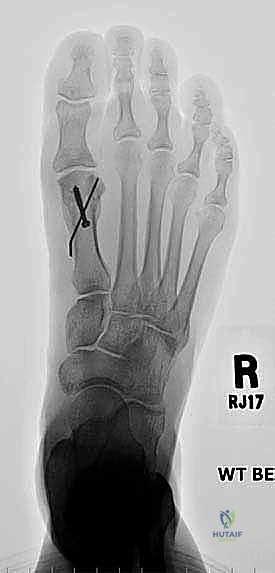

2. التصوير الشعاعي المتقدم

التصوير هو ما يظهر الحجم الحقيقي للمشكلة الهيكلية.

* الأشعة السينية العادية (X-rays) أثناء الوقوف: هذا هو الفحص الأهم. يتم أخذ صور للقدمين أثناء تحمل الوزن لقياس زوايا العظام بدقة، وتحديد مقدار النقص في طول مشط القدم الأول مقارنة بالثاني (يجب أن يكونا متقاربين في الطول ضمن نسب محددة).